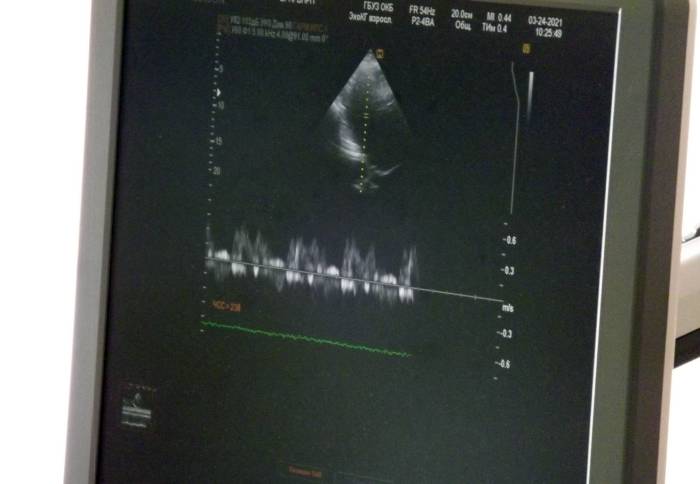

Для оценки структуры сердца применяют эхо-ЭКГ. Его задача – оценить размеры полостей сердца, сократимость, состояние клапанного аппарата. Это затратная методика по объему и по времени, так как может длиться от 30 минут до полутора часов. К тому же, требуется время и на обработку результатов.